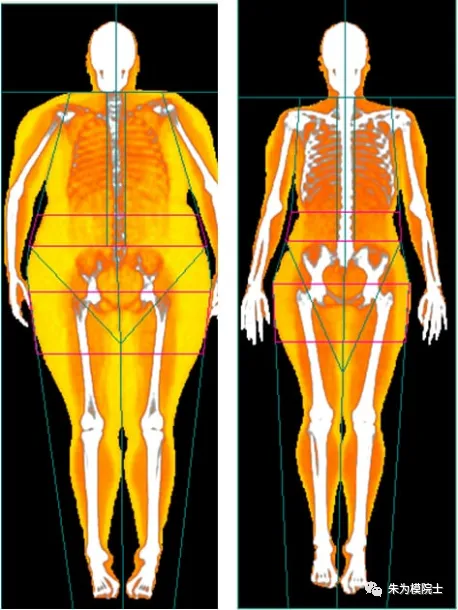

2. 人的脂肪一开始是存在于皮下,过多后开始向全身包括肝脏和胰腺转移。